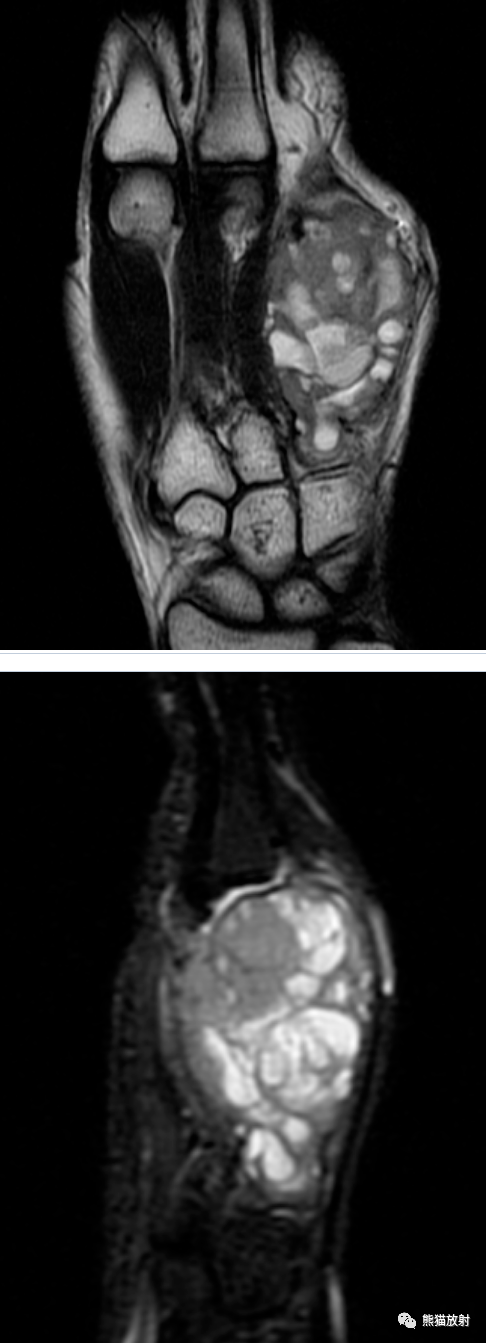

手部肿物之丨非好发部位但表现典型